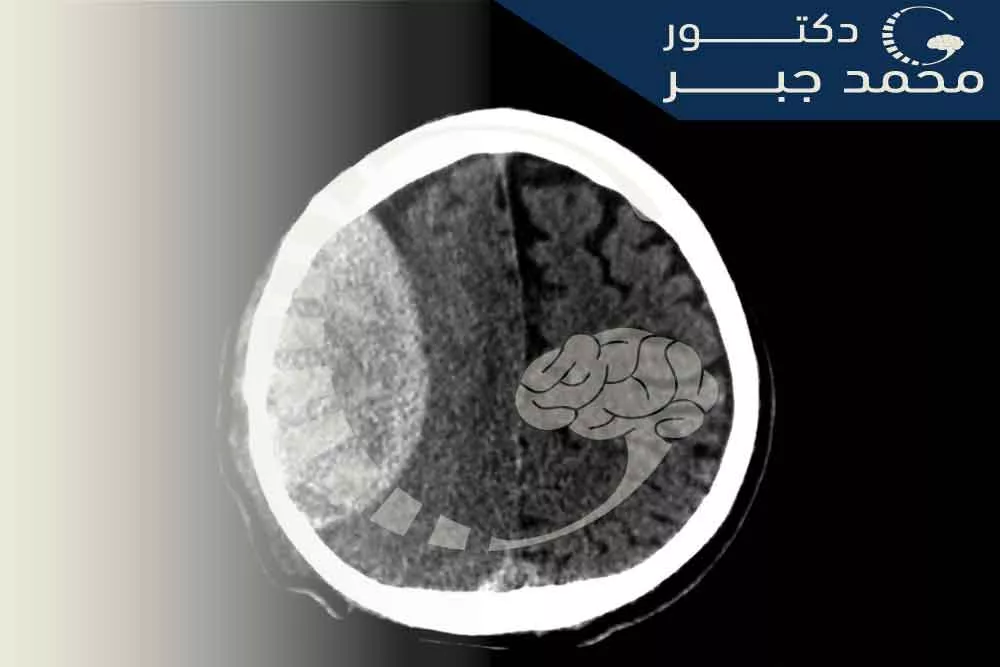

ุงููุฑู ุงูุฏู ูู ุฃู ู ุง ูุนุฑู ุจูุฒูู ุชุญุช ุงูุฌุงููุฉ ูู ููุน ู ู ุฅุตุงุจุงุช ุงูุฏู ุงุบ ุงูุชู ุชุญุฏุซ ุนูุฏู ุง ูุชุฌู ุน ุงูุฏู ุจูู ุงูุณุทุญ ุงูุฏุงุฎูู ููุฌู ุฌู ุฉ ูุงูุทุจูุฉ ุงูุฎุงุฑุฌูุฉ ููุฏู ุงุบุ ูุงูุชู ุชุณู ู ุงูุฃู ุงูุฌุงููุฉ.

ูุญุฏุซ ุงููุฒูู ุงูุฏู ูู ุชุญุช ุงูุฃู ุงูุฌุงููุฉ ุจูุณุจุฉ ุญูุงูู 25% ู ู ุงูุฃุดุฎุงุต ุงูู ุตุงุจูู ุจุฅุตุงุจุงุช ุงูุฑุฃุณ ุญูุซ ุชุฑุชูุน ูุณุจุฉ ูุฌุงุญ ุนู ููุงุช ูุฒูู ุงูู ุฎ

ุงุฎุชุจุงุฑุงุช ุงูุชุตููุฑ: ูุชุฃููุฏ ุชุดุฎูุต ุงููุฒูู ุฃู ุงููุฑู ุงูุฏู ูู ุชุญุช ุงูุฌุงููุฉุ ูุชุญุฏูุฏ ุญุฌู ูุ ูู ููุนู. ุชุดู ู ุงุฎุชุจุงุฑุงุช ุงูุชุตููุฑ ุงูุฃูุซุฑ ุดููุนูุง ู ุง ููู: ุงูุชุตููุฑ ุงูู ูุทุนู ุงูู ุญูุณุจุ ุงูุชุตููุฑ ุจุงูุฑููู ุงูู ุบูุงุทูุณู.